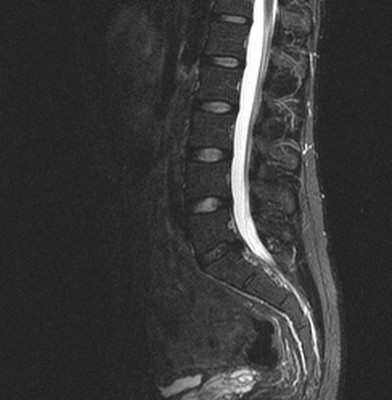

МРТ поясничного отдела позвоночника. Т2-взвешенная сагиттальная МРТ. Дегенеративные изменения дисков. Цветовая обработка изображения.

Понятие нормы для позвоночника в МРТ изображении довольно условно. Считается, что диск в норме двояковыпуклый, пульпозное ядро светлое на Т2-зависимых МРТ изображениях, в центре может быть горизонтальная линия соединительной ткани.

Термин “дегенеративные изменения позвоночника” обобщает целый ряд заболеваний.

С третьей декады жизни начинается постепенная дегидратация межпозвоночного диска с потерей им эластичности. Увеличивается соотношение кератин сульфат/хондроэтин сульфат и среди хондроэтинов также меняется соотношение в пользу хондроэтин-4-сульфата. Снижается синтез и уменьшается концентрация протеогликанов и неколагеновых протеинов. Деполимеризация мукополисахаридов приводит к потереводы. Поступление в диск кислорода и питающих веществ ухудшается, а продукты обмена, наоборот, накапливаются. Происходит постепенная дегидратация межпозвоночного диска. Пульпозное ядро накапливает коллаген, и замещается фибрознохрящевой тканью. Процесс начинается с задней части диска, затем распространяется на весь диск, граница пульпозного ядра и фиброзного кольца стирается. Это может быть названо термином остеохондроз. Диск теряет эластичность. Снижение давления внутри диска приводит к засасыванию азота в ядро и возникновению пузырей - “вакуум-феномена”, наиболее отчетливо видимого при КТ.